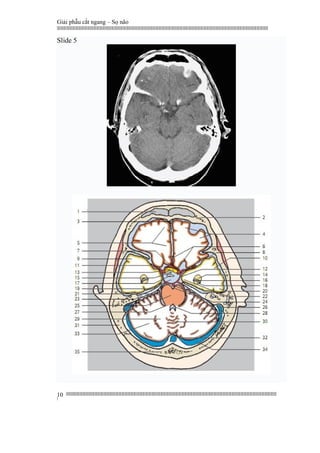

Slide 5

1. Frontal sinus

2. Frontal bone

3. Falxcerebri

4. Orbital gyri

5. Straight gyrus

6. Anterior cerebral artery

7. Anterior communicating artery

8. Internal carotid artery

9. Superior temporal gyrus

10. Middle temporal gyrus

11. Middle cerebral artery

12. Posterior communicating artery

13. Opticchiasm

14. Amygdaloid body

15. Pituitary stalk

16. Lateral ventricle (temporal horn)

17. Dorsum sellae

18. Hippocampus

19. Pentagon of basal cisterns

20. Inferior temporal gyrus

21. Posterior cerebral artery

22. Parahippocampal gyrus

23. Tentorium cerebelli

24. Basilar artery and basal sulcus

25. Pons

26. Sigmoid sinus

1. Xoang trán

2. Xương trán

3. Phần trước liềm đại não

4. Hồi ổ mắt

5. Hồi thẳng

6. Động mạch não trước

7. Động mạch thông trước

8. Động mạch cảnh trong

9. Hồi thái dương trên

10. Hồi thái dương giữa

11. Động mạch não giữa

12. Động mạch thông sau

13. Giao thoa thị giác

14. Thể hạnh nhân

15. Cuống tuyến yên

16. Sừng thái dương não thất bên

17. Lưng yên

18. Hồi hải mã

19. Hội lưu của các bể nền sọ

20. Hồi thái dương dưới

21. Động mạch não sau

22. Hồi cạnh hải mã

23. Lều tiểu não

24. Động mạch thân nền và rãnh nền

25. Cầu não

26. Xoang tĩnh mạch sigma

27. Cerebellar peduncle (middle)

28. Fourth ventricle

29. Dentate nucleus

30. Vermis of cerebellum (superior part)

31. Temporal bone

32. Confluence of the sinuses

33. Cerebellarhemisphere

34. Transverse sinus

35. Occipital bone

27. Cuống tiểu não giữa

28. Não thất tư

29. Nhân răng tiểu não

30. Thùy nhộng tiểu não

31. Xương thái dương

32. Hội lưu xoang

33. Bán cầu tiểu não

34. Xoang ngang

35. Xương chẩm.